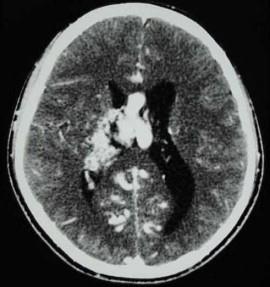

问题 男,32岁,头痛、癫痫,查体发现视乳头水肿,CT检查如图,最可能的诊断为()

选项 A.结节状硬化 B.钙化灶 C.动静脉畸形 D.少突胶质瘤 E.脑囊虫

答案 C